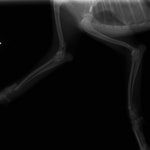

症例3:キルシュナーワイヤーのピンニングによる整復

ペルシャ猫 11ヶ月齢 雄

他院にて左大腿骨遠位の成長板骨折(salter-harrisⅠ型)が認められており、治療相談を目的として来院。当院にて、キルシュナーワイヤーを用いたピンニングにより骨折部位の整復を行いました。術後の経過は良好で、現在も経過観察中です。

術前レントゲン

術後レントゲン

機器

Arthrex社のターゲティングデバイスを用いてピンニングの位置を調整することで、確実な固定を行っています。当院ではこの手術器具以外にも、人の手術にも使用される様々な器具を導入し、手術精度を高め、また医療メーカーと新しい器具の開発、試作にも取り組んでおります。